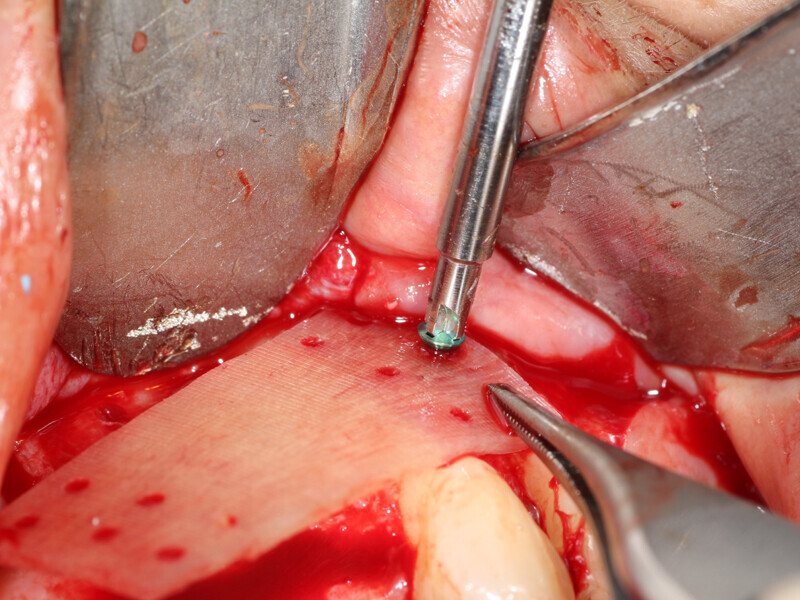

Fig. 4: The facial plate is fenestrated with a bur through the cortical bone in the edentulous space that will receive the osseous graft.